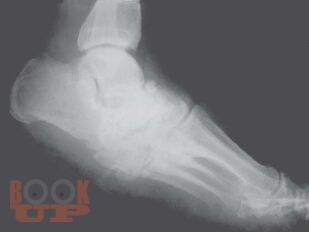

В руководстве обобщён 25-летний опыт хирургического лечения 705 больных с гнойно-некротическими осложнениями синдрома диабетической стопы. Кратко сформулирована концепция патогенеза диабетической стопы. Представлена клиника, диагностика, а также способы хирургического лечения заболеваний, объединяемых понятием “диабетическая стопа”. Изложена современная тактика активного хирургического лечения гнойной инфекции. Описаны и иллюстрированы известные и оригинальные, органосберегающие и ампутационные хирургические операции на нижних конечностях, предназначенные для лечения гнойно-некротических осложнений диабетической стопы. Разработаны способы закрытия операционных ран съёмными дренирующими, малоишемизирующими и тензионными швами, снижающими вероятность послеоперационных осложнений. Приведены методы ангиопротективного лечения и хирургической реваскуляризации, предназначенные для коррекции нейроишемии. Автор разработал и, вероятно, впервые применил патогенетически обоснованные оперативные вмешательства для лечения осложнённой диабетической нейроостеоартропатии Шарко. Даны практические рекомендации, направленные на снижение послеоперационных осложнений и летальности. Созданы объективные критерии для выбора уровня ампутации стопы и голени. Предложена новая классификация осложнений СДС, отражающая клинические формы, степени ишемии, тяжесть и глубину поражения тканей, помогающая ориентироваться в вопросах лечебно-прогностического характера.